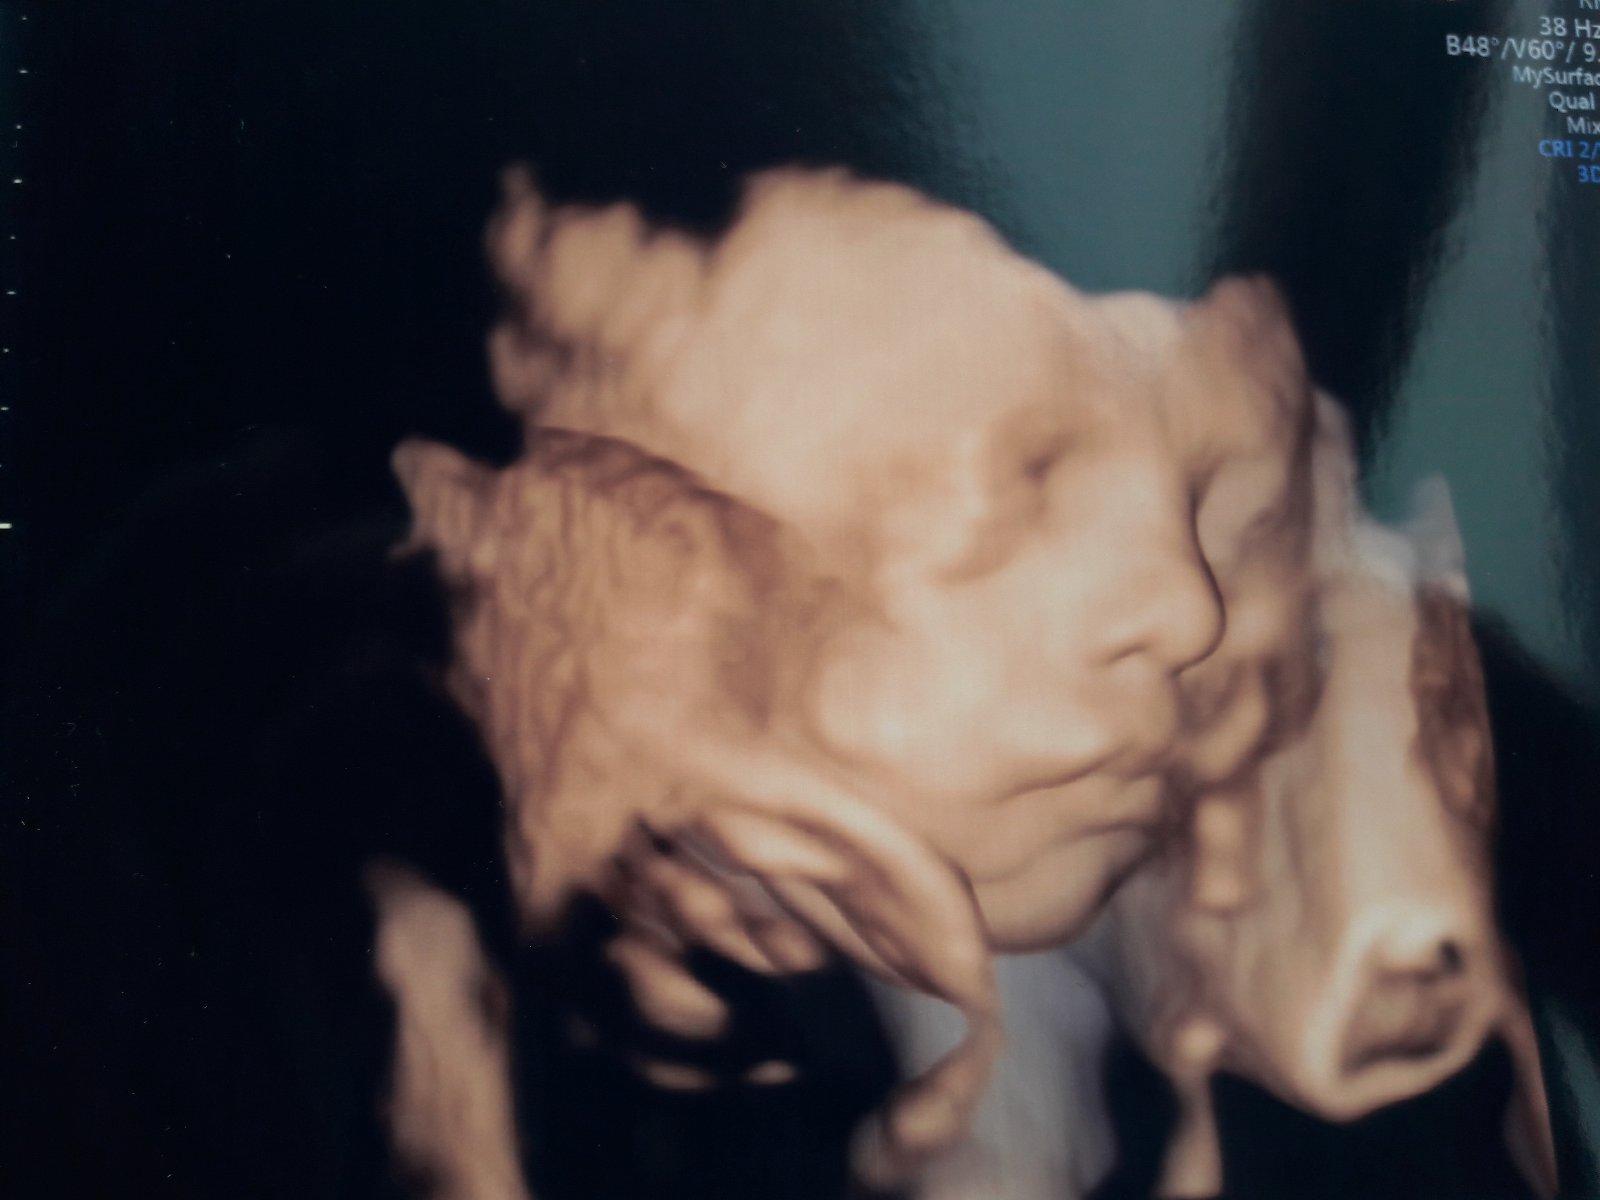

@walentinka krasny je ...a kolko uz vazi? Moj mal pred tyzdnom ked sme boli na 3d 1600g cca 🙂

@moskova1983 my sme boli dnes a ma okolo 1505 gramov 🙂 tvoj je vacssi macko 🙂

@walentinka hej doky vravel ze sme o tyzden vacsi hlavne ze zdravucky ❤

@moskova1983 fakt je to krasne